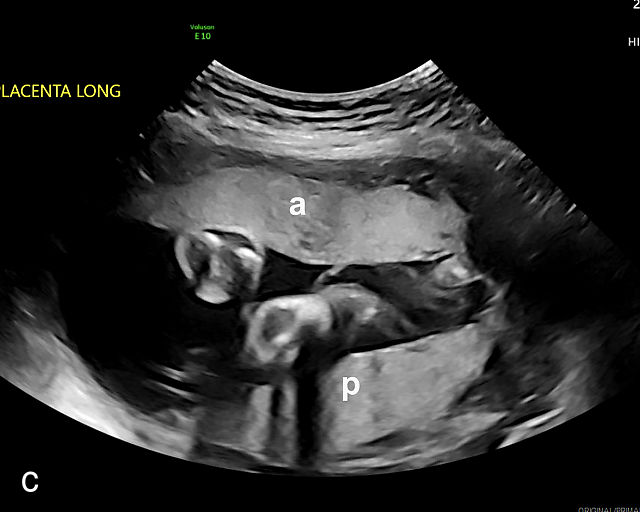

4

Accessory placental lobes. (a) Color Doppler transabdominal ultrasound image depicting a bilobed placenta with an anterior (a) and posterior (p) lobe, into which the cord inserts. (b) Grayscale ultrasound with color flow Doppler showing a bilobed placenta with anterior (a) and posterior (p) lobes. Color flow Doppler shows unprotected fetal vessels traversing the membranes between the lobes (arrow). (c) Grayscale ultrasound showing a bilobed placenta with anterior (a) and posterior (p) lobes.

The sonographic features of a bilobed or succenturiate-lobed placenta include the presence of two distinct placental masses, typically one anterior and the other posterior, which may vary in size or be of equal size.21,22,23,24,26,31,32,33 These masses are connected by blood vessels, which can be visualized using color flow Doppler (Figure 4).28

It is crucial to confirm that the masses are truly separate and not connected as part of a single lateral placenta, which may be mistaken for a bilobate placenta. Additionally, careful scanning should verify that both masses share similar echogenicity to distinguish true placental tissue from other structures such as subchorionic hematomas, myometrial contractions or uterine fibroids, which can mimic accessory lobes. Prominent placental lakes may also be observed between the lobes.23,26